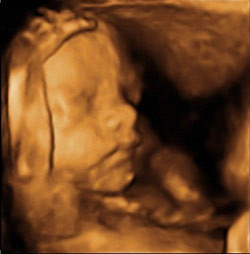

Ecografía tridimensional 3D y 4D